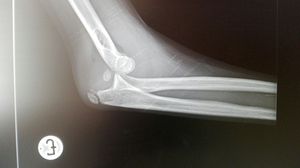

Xray

Dislocation

Elbow